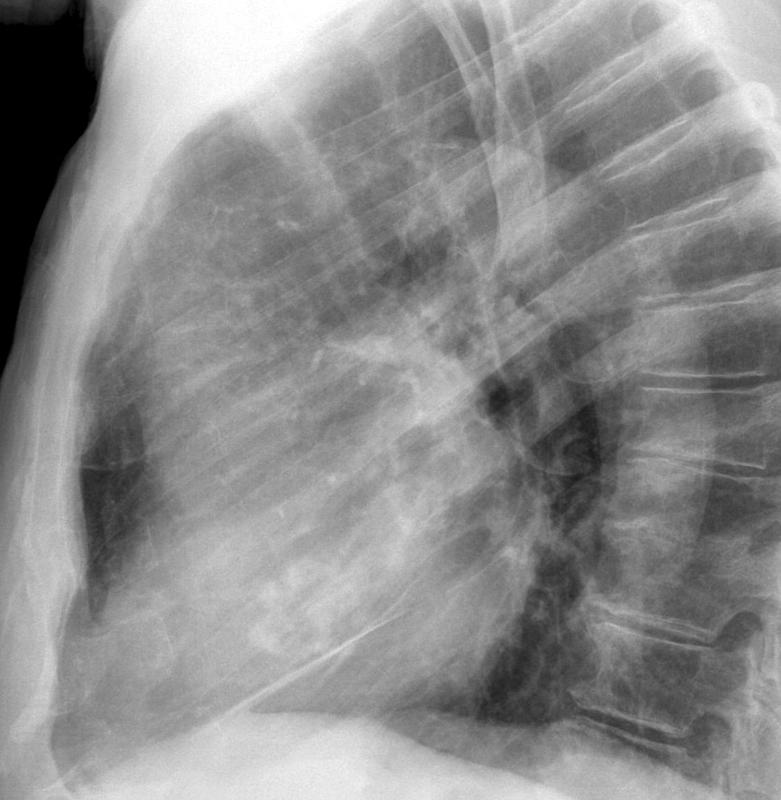

calcif Ao valve